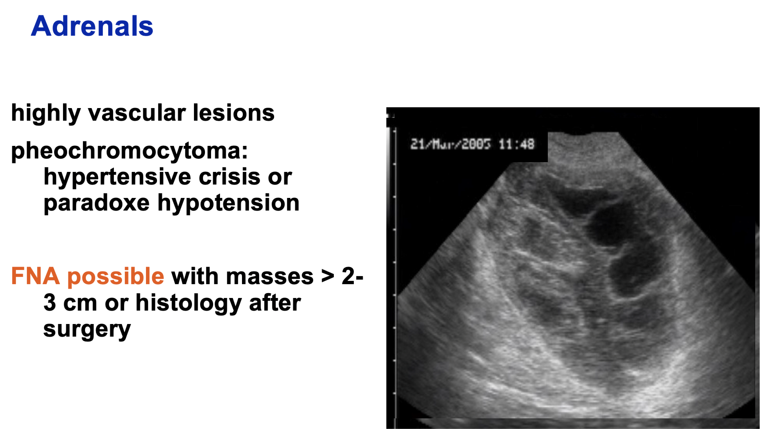

What types of lesions should you FNA? (4)

A

Cyst

Small solid lesion

Highly vascular lesion

Diffuse infiltrative lesion

Q

Adrenal biopsy technique.